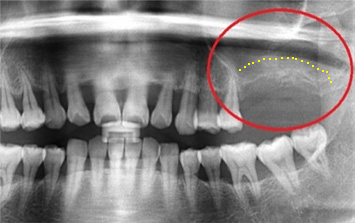

아래턱 어금니 발치 후 장시간 방치하여 잇몸 뼈 소실이 심한 상태로 내원. 뼈 이식 후 임프란트를 식립하였습니다.

잇몸 뼈 소실이 심한 상태로 내원